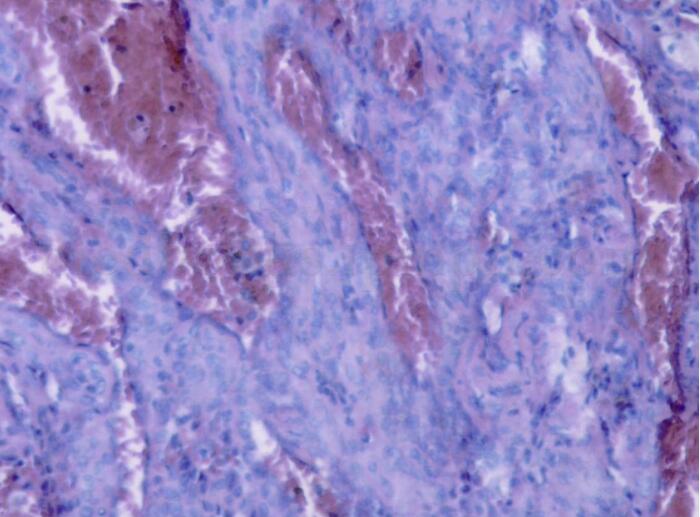

左肺下叶硬化性血管瘤(图2)

图2瘤细胞大部分排列成大小不等血管样,少部分区域呈乳头状,实性片状排列,部分细胞圆形,部分细胞立方状。病理诊断:左肺下叶硬化性血管瘤